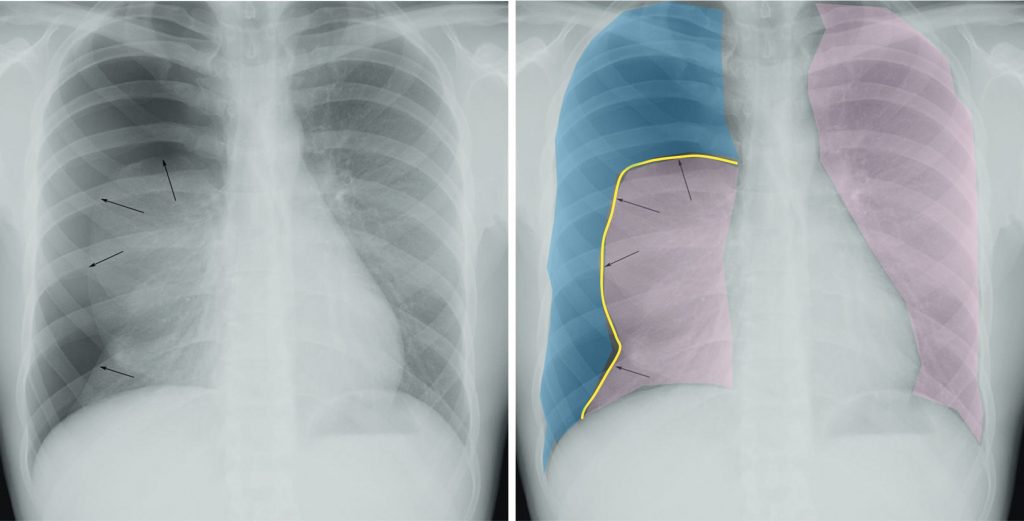

La radiographie thoracique montre que le bord externe de la plèvre pulmonaire, sous la forme d’une fine ligne qui croise l’arc postérieur des côtes, est séparé de la paroi par un croissant gazeux clair avasculaire (figures 98.1 et 98.2). Les signes de pneumothorax sous-tension (figure 98.3) sont un déplacement médiastinal vers le côté opposé, un aplatissement de la coupole diaphragmatique homolatérale, une expansion de la cage thoracique et un poumon dense collabé au hile.

Fig. 98.1. Radiographie de face. Pneumothorax droit spontané d’abondance moyenne.

En pratique clinique, il est important de noter que le diagnostic de dépistage radiologique d’un pneumothorax repose principalement sur l’analyse des vaisseaux intrapulmonaires, plus que sur l’aspect proprement dit de la cavité pleurale, même si cette dernière correspond de fait au site d’atteinte. Cette analyse par les vaisseaux est ainsi plus performante dans la détection des décollements pleuraux, notamment lorsque ceux-ci sont de faible abondance. La figure montre une radiographie thoracique de face, avec à gauche l’image native et à droite une schématisation en couleur des zones d’intérêts à analyser, que sont les poumons (en beige), la plèvre viscérale (ligne jaune) et la cavité pleurale (en bleu). La lecture pratique de l’imagerie se fait de la façon suivante :

– au niveau du poumon gauche normal, les vaisseaux intrapulmonaires normaux sont visibles sous la forme d’opacités tubulaires ramifiées et visibles du hile jusqu’en périphérie du poumon. Il n’y a donc pas de décollement pleural ;

– au niveau du poumon droit décollé, les vaisseaux intrapulmonaires sont visibles à partir du hile mais uniquement jusqu’au niveau d’une interface croisant les côtes (ligne jaune, flèches noires), puis non visibles au-delà en périphérie. Cet aspect indique la présence d’un décollement pleural, visible sous la forme d’une interface entre la plèvre viscérale qui entoure le poumon (schématisé en beige) et la cavité pleurale remplie d’air. Cette cavité pleurale remplie d’air est ainsi visible sous la forme d’une hyperclarté, en forme de croissant gazeux avasculaire, schématisée en bleu.

Source : CERF, CNEBMN, 2022.